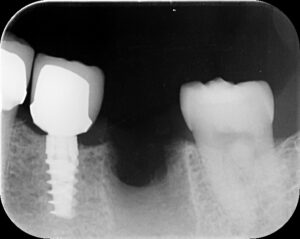

抜歯後2週間で骨増生した症例。